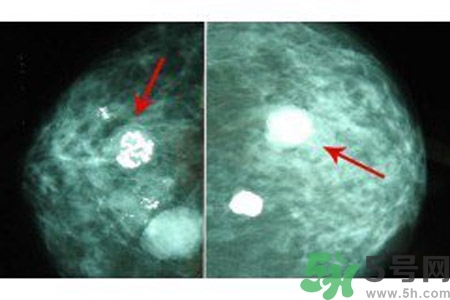

鈣化形態(tài)對(duì)辨別病變的良惡性有較大的意義,在觀察中發(fā)現(xiàn)。

顆粒狀、蛋殼狀、不規(guī)則團(tuán)塊狀及軌道狀鈣化多發(fā)生于良性病變。

針尖狀、小桿狀、分叉狀及泥沙樣鈣化多發(fā)生于惡性病變,鈣化的形式多樣、大小差異很大時(shí),惡性的可能性越大,單純出現(xiàn)一種形態(tài)的鈣化時(shí),成簇的針尖狀、分叉狀鈣化,對(duì)診斷惡性病變的意義較大。而單純出現(xiàn)泥沙樣鈣化,對(duì)病變的良惡性判別則比較困難。泥沙樣鈣化為不確定性鈣化,良惡性有重疊,但如果泥沙樣鈣化伴有其他鈣化形式,提示惡性病變。

乳腺鈣化數(shù)目

良性鈣化一般數(shù)目少,顆粒粗大。惡性病變表現(xiàn)為數(shù)目多,甚至無法計(jì)數(shù),如泥沙樣鈣化、成簇的針尖樣鈣化。但有時(shí)也可表現(xiàn)為數(shù)量較少,數(shù)顆或數(shù)十顆,數(shù)目少的惡性鈣化常見于分叉狀、小桿狀。1972年Woife提出15~20個(gè)/cm2個(gè)鈣化點(diǎn),即可判斷為惡性鈣化。

乳腺鈣化部位

了解鈣化部位應(yīng)強(qiáng)調(diào)多方位、多角度觀察。良性鈣化灶,多發(fā)生在纖維組織、脂肪、血管、大汗腺、皮膚等乳腺間質(zhì)內(nèi),乳腺實(shí)質(zhì)內(nèi)少見。惡性鈣化則多發(fā)生于乳腺實(shí)質(zhì)內(nèi),泥沙樣鈣化多發(fā)生在乳腺小葉腺泡內(nèi),小桿狀鈣化多發(fā)生在導(dǎo)管內(nèi),小叉狀鈣化則多位于末支小導(dǎo)管內(nèi)。

乳腺鈣化與腫塊的關(guān)系

鈣化可與腫塊并存,也可獨(dú)立存在;既可發(fā)生在病變內(nèi),也可獨(dú)立于腫塊之外。90%的導(dǎo)管原位癌是通過X線鉬靶照片發(fā)現(xiàn)的,且僅以乳腺內(nèi)鈣化作為惟一的表現(xiàn)形式。這是由于原位癌中央發(fā)生不規(guī)則壞死引起的鈣鹽在導(dǎo)管內(nèi)沉積或腫瘤細(xì)胞分泌而呈形態(tài)各異的的表現(xiàn)。